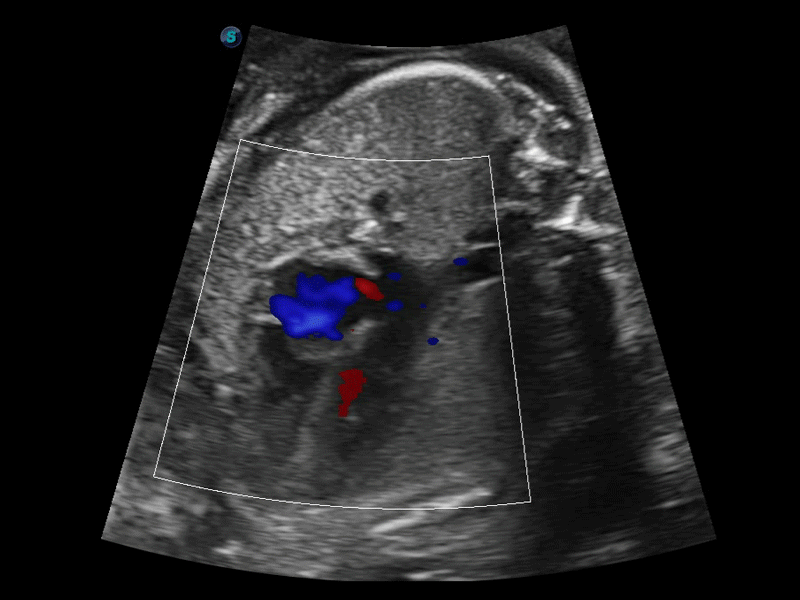

開立醫(yī)療通過不斷的技術(shù)創(chuàng)新,為大眾的生命健康提供持續(xù)關(guān)愛。P12 Plus采用全新一代超聲成像平臺(tái),新平臺(tái)旨在將真實(shí)還原組織解剖結(jié)構(gòu)作為首要目標(biāo)。平臺(tái)采用全新集成化硬件模塊,搭載新一代芯片,系統(tǒng)性能得到大幅提升,為您的診斷提供了豐富的臨床信息。優(yōu)異的圖像表現(xiàn),豐富的探頭配置,全面的應(yīng)用功能,為您日常診斷提供了可靠的助手。

P12 Plus

彩色多普勒超聲診斷系統(tǒng)